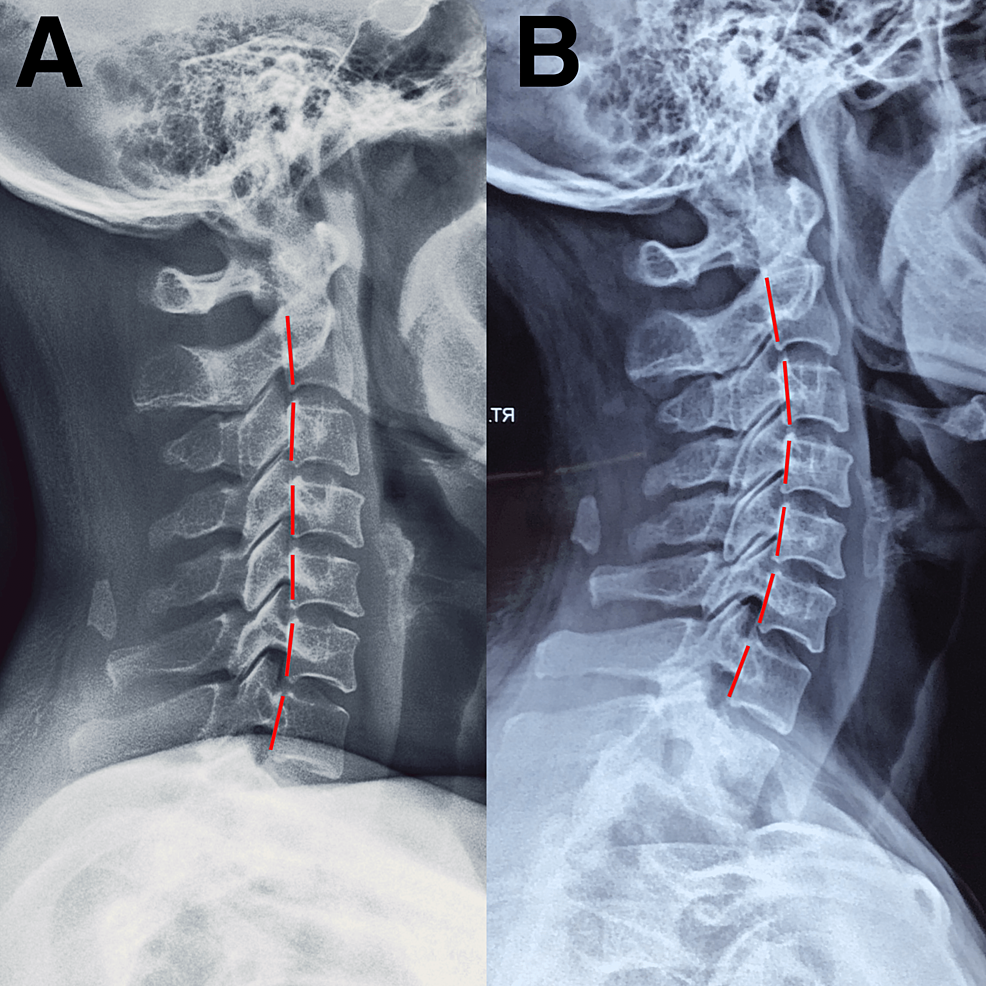

From www.cureus.com

Cervicogenic Dizziness After SelfManipulation of the Cervical Spine Cervical Spine Dizziness Reddit A place to discuss and explore cervical vertigo and cervicogenic dizziness. People with cervical vertigo (or cervicogenic dizziness) experience neck pain, as well as dizziness. Please help enlighten and encourage others as they struggle with this. Cervicogenic dizziness (cgd) is a clinical syndrome characterized by the presence of dizziness and associated neck pain. A place to discuss and explore cervical. Cervical Spine Dizziness Reddit.